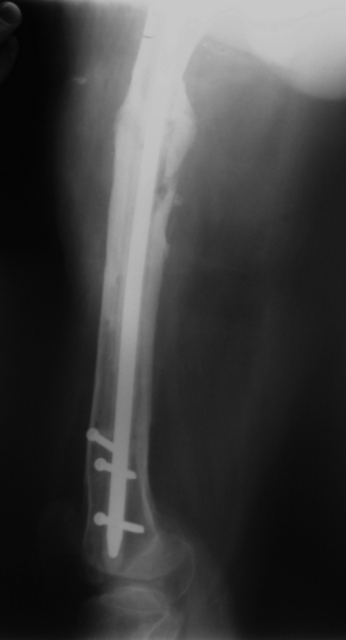

[Ortho] Proximal femoral shaft nonunion + osteomyelitis

Вчера наш пациент был на контрольном осмотре. Вроде все идет нормально. Рентгенограммы от 25 сентября 2007 г. (прошло 5 месяцев после операции) прилагаю.

Имя     : 1.jpg

Тип     : image/jpeg

Размер  : 67329 байтов

Url     : http://weborto.net:8080/pipermail/ortho/attachments/20070926/c7cc77e9/attachment-0002.jpg